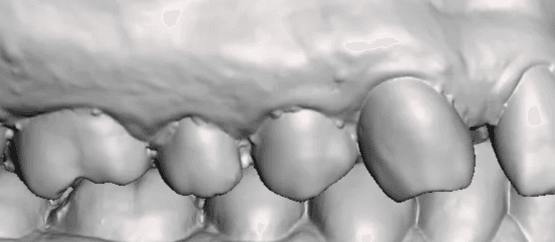

Falha de “Costura”

O escaner funciona tirando varias fotos da boca e vai “costurando” uma com a outra, formando uma imagem 3D, como se estivesse tecendo uma malha de tecido, tanto que é muito comum usar o termo “Malha” para se referir a um escaneamento 3D.

É muito comum você ter um defeito nessa junção da malha vestibular e lingual nas incisais Bateria Labial (tanto superior quanto inferior), esse defeito também conhecido como “falha de costura”.

Apesar de parecer um defeito pequeno ele pode prejudicar a adaptação do alinhador fatalmente por um lado da boca não ter alinhamento com o outro.